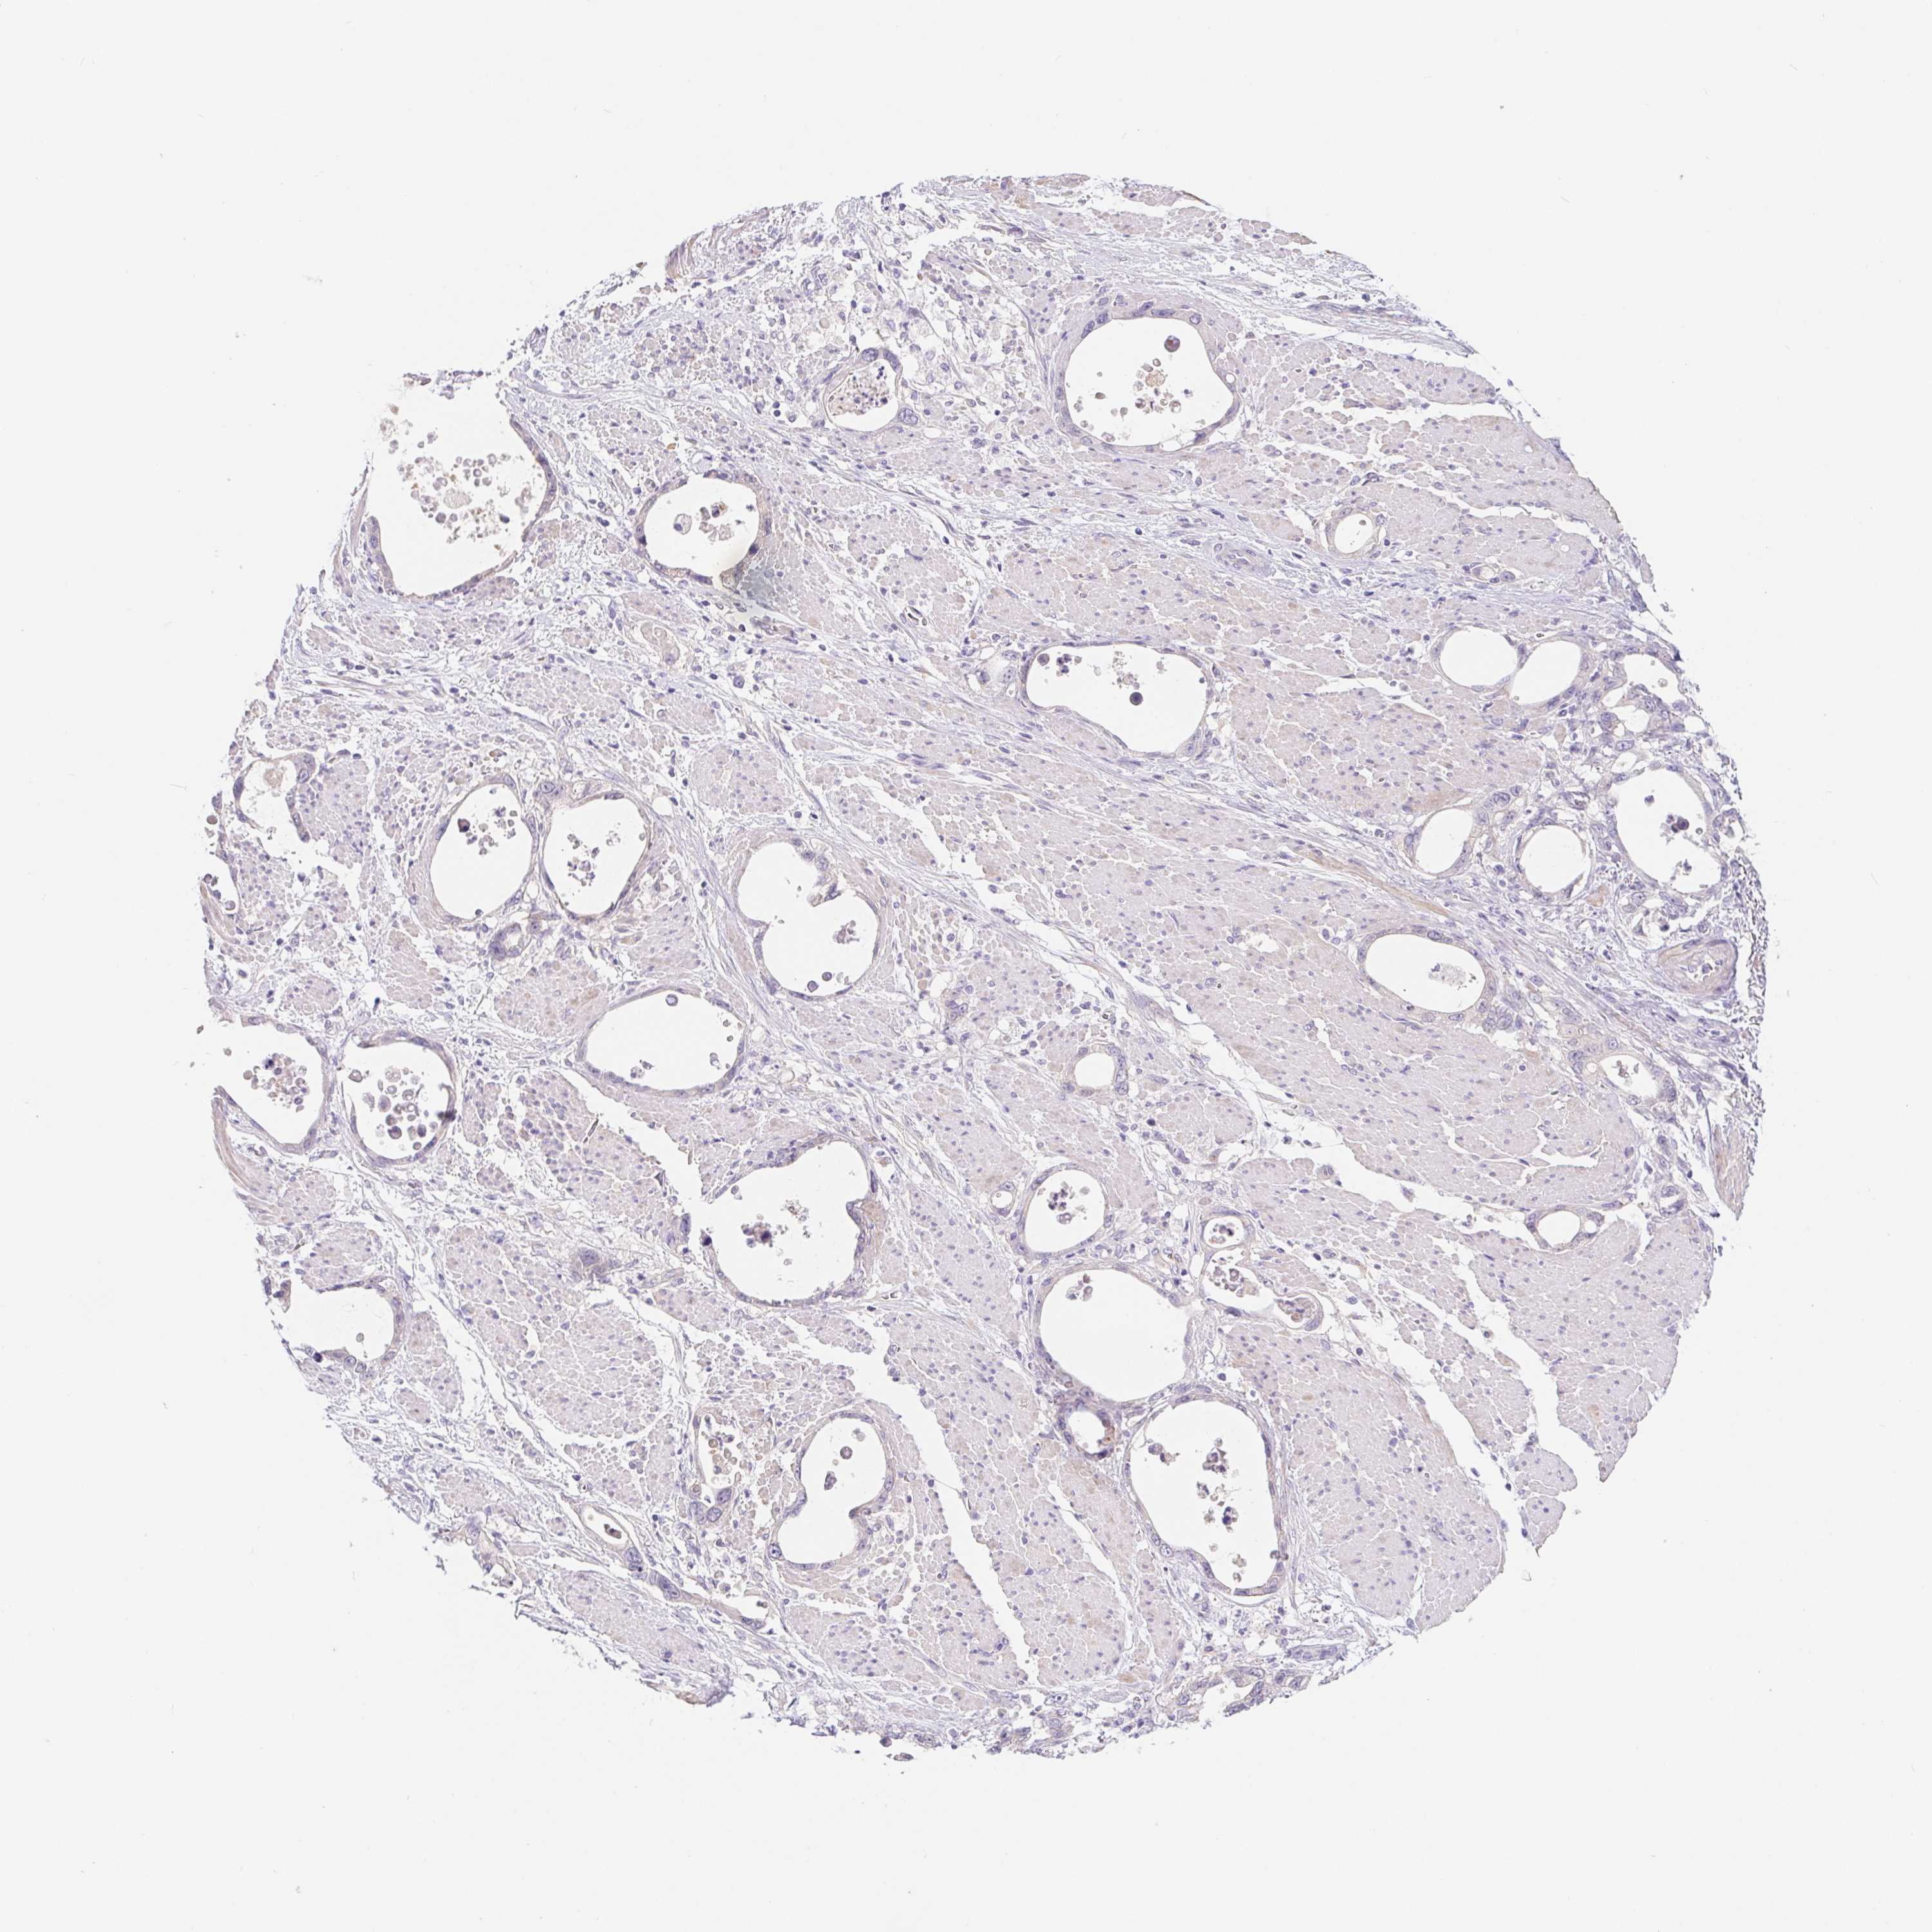

STOMACH CANCER - Protein expressioni

A mouse-over function shows sample information and annotation data. Click on an image to view it in a full screen mode. Samples can be filtered based on level of antibody staining by selecting one or several of the following categories: high, medium, low and not detected. The assay and annotation is described here.

Note that samples used for immunohistochemistry by the Human Protein Atlas do not correspond to samples in the TCGA dataset.

Antibody stainingi

Antibody staining in the annotated cell types in the current human tissue is reported as not detected, low, medium, or high, based on conventional immunohistochemistry profiling in selected tissues. This score is based on the combination of the staining intensity and fraction of stained cells.

Each image is clickable and will lead to virtual microscopy that enables deeper exploration of all samples and also displays staining intensity scores, fraction scores and subcellular localization as well as patient and tissue information for each sample.

Antibody HPA062905

Staining

High

Medium

Low

Not detected

Intensity

Strong

Moderate

Weak

Negative

Quantity

>75%

75%-25%

<25%

None

Location

Nuclear

Cytoplasmic/membranous

Cytoplasmic/membranous,nuclear

Adenocarcinoma, NOS